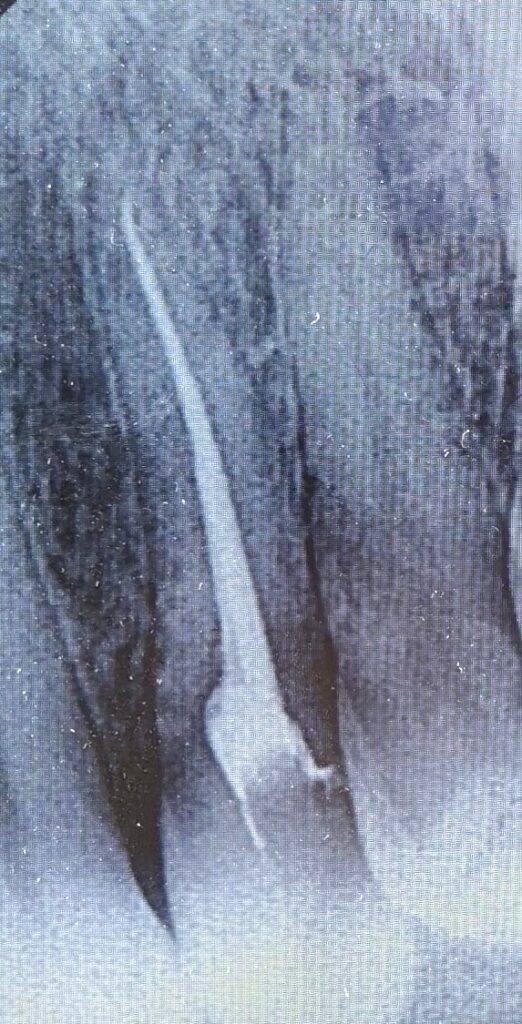

Introduction: In the field of dentistry, root canal treatment plays a crucial role in saving teeth affected by irreversible pulpitis. This blog is a a case study involving a 19-year-old patient Sumaira who presented with severe toothache and underwent successful root canal treatment. Case Presentation: The patient, a 19-year-old female, visited the clinic with a […]